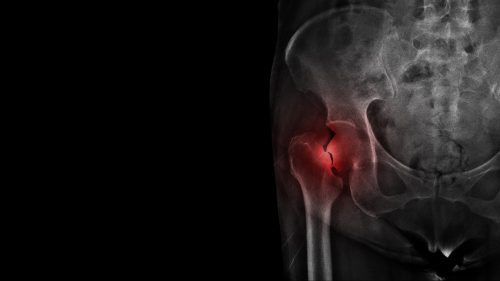

What Is an Intracapsular Hip Fracture, and Why Is It So Serious?

An intracapsular hip fracture occurs at the neck of the femur, within the capsule that contains the fluid your body uses to keep your hip joint moving smoothly. When this area is broken, it is not just the damaged bone that is damaged. Instead, the fracture can disrupt critical blood flow, risking long-term complications like avascular necrosis (bone death), permanent mobility loss, or even fatal blood clots in vulnerable patients.